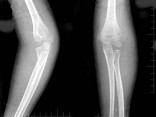

[单选题]女,6岁,外伤后左肘部肿痛,活动受限,外髁局部压痛,X线摄片如图,最可能的诊断是()A .左肱骨小头骨骺损伤B .左肱骨髁上骨折C .左肱骨外上髁骨骺损伤D .左肱骨内髁骨骺损伤E .左肱骨外髁骨骺损伤

[单选题]6岁女性患者,因外伤后致左肘关节肿痛,活动受限,外髁局部压痛明显X线摄片如图,最合适的诊断是()A . 左肱骨小头骨骺Ⅰ度分离B . 左肱骨小头骨骺Ⅱ度分离C . 左肱骨小头骨骺Ⅲ度分离D . 左肱骨小头骨骺Ⅳ度分离E . 左肱骨小头骨骺Ⅴ度分离